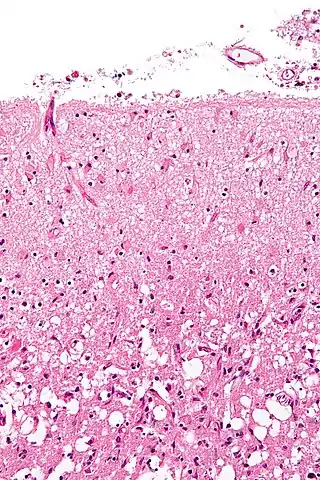

La astrogliosis (también conocida como astrocitosis o astrocitosis reactiva) es un aumento anormal en el número de astrocitos debido a la destrucción de las neuronas próximas por un trauma en sistema nervioso central (SNC), infección, isquémia cerebral, un accidente cerebrovascular, una respuesta autoinmune y una enfermedad neurodegenerativa. En el tejido neuronal saludable, los astrocitos desempeñan un papel crítico al proporcionar energía a las neuronas, regular el flujo sanguíneo, la homeostasis del fluido extracelular así como de los iones y transmisores, y regular la función sináptica y el remodelado sináptico.[1][2] La astrogliosis cambia la expresión molecular y la morfología de los astrocitos, provocando la formación de cicatrices y, en casos graves, la inhibición de la regeneración de axones.[3][4]

![]() Formación de astrocitos reactivos después de una lesión al sistema nervioso central | ||

La astrogliosis es un conjunto de cambios en los astrocitos que ocurren como respuesta a todas las formas de daño y enfermedad del SNC. Los cambios producidos por la astrogliosis reactiva varían con la gravedad del daño ocasionado al SNC a lo largo de una serie de alteraciones progresivas en la expresión molecular, hipertrofia celular progresiva y la proliferación y formación de cicatrices.[3]